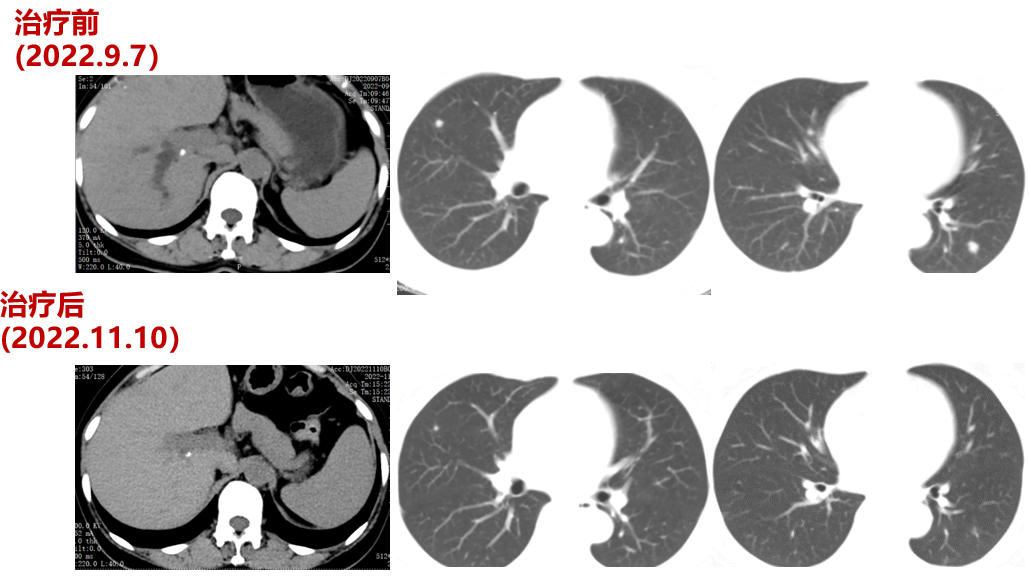

二线治疗(2021-12至2022-8-3,二线PFS:7月余):

于2021-12-03、2021-12-27给予伊尼妥单抗+吡咯替尼方案治疗2周期。2022.1.19始给予患者伊尼妥单抗+吡咯替尼+替雷利珠单抗治疗,两周期,四周期时的疗效评估可以看到,肺上病灶明显缩小,甚至有的病灶消失,肿瘤标志物也在持续下降。

肿瘤第二次进展(2022-8-3):在二线治疗7月余后,肿瘤标志物升高,CT也显示,肺上的病灶增大,患者双靶向+免疫治疗进展。

三线治疗(2022-9-7至2023-03-18,PFS:6月余):

2022-09-07至2023-01-03院外使用DS-8201治疗5周期。2周期后疗效评价:PR。CT示:腹膜后淋巴结较前部分缩小;双肺多发转移灶较前缩小。